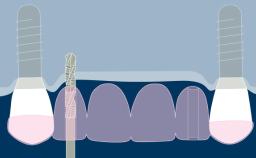

- descrever como os biofilmes microbianos se formam nos implantes e levam à inflamação do tecido mole peri-implantar e do osso de suporte

- identificar os efeitos da inflamação nos tecidos moles peri-implantares e no osso de suporte